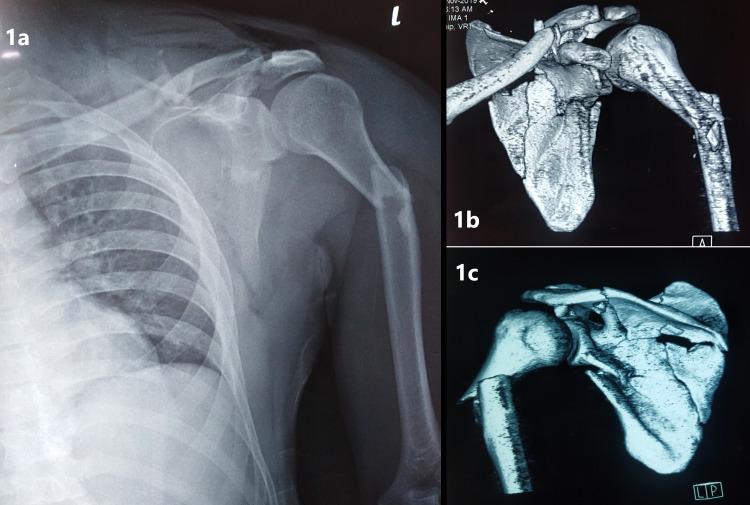

Simultaneous ipsilateral fractures involving all the bones around the shoulder girdle, namely, the scapula, clavicle and humerus, are rare. We describe an interesting case of a 31-year-old patient who presented after a motor vehicle accident with excruciating pain over his left shoulder and a flail left upper limb. Radiographs and computed tomography (CT) scan revealed the presence of comminuted left scapula, clavicle and proximal humerus fractures. He was also diagnosed with a complete brachial plexus injury of the left shoulder. The patient underwent a tedious surgery involving screw fixation and plating of the scapula, clavicle and proximal humerus. Despite achieving stable fixations of the shoulder and radiographic union of all the fractures, he did not recover from the complete brachial plexus injury 14 months after the trauma. The presence of ipsilateral clavicle, scapula and humerus fracture suggests involvement in high-energy trauma, and therefore, associated injuries especially neurovascular compromise should not be missed. Despite its rarity, management of this complex injury should always be individualised to ensure optimal functional outcomes are achieved.